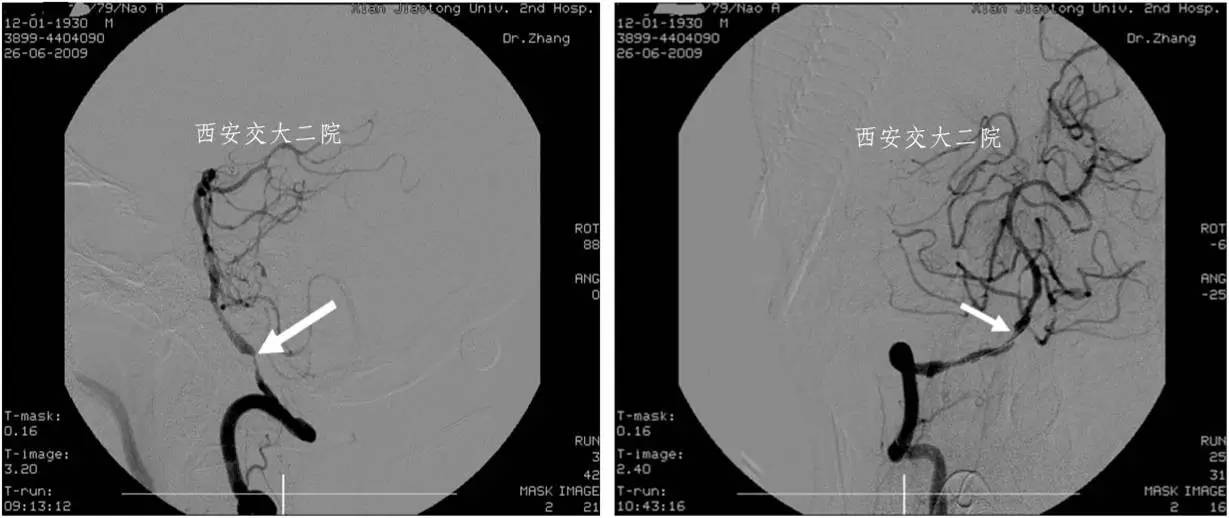

Case 5 椎动脉颅内段狭窄支架成形术(2009年)

》男,79岁,发作性头晕1年余,曾多次住院用药效果不佳。

》DSA:1.左椎闭塞;2.右椎v4段狭窄90%;至2014年3月随访58月,mRS评分1级。